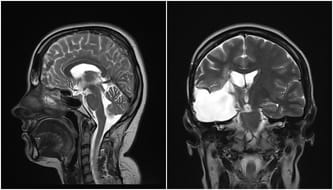

Lekarze wykonali mi tomografię komputerową. Na moim mózgu wyrósł olbrzymi guz. To on, a nie zmęczenie, był przyczyną wszystkich bólów głowy. Kiedy usłyszałam, że mam raka, tę najstraszniejszą z chorób, której sama nazwa wzbudza lęk, próbowałam to wszystko wyprzeć. Myślałam, że to tylko zły sen, że zaraz się obudzę. Przecież takie rzeczy się nie zdarzają, nie tak młodym ludziom, nie mnie… Pamiętam nerwowe szepty lekarzy, szloch mamy i zapadające jedna po drugiej decyzję. Czułam, że gdzieś na szali waży się moje życie, a ja na nic nie mam wpływu. Zdecydowano, że trzeba natychmiast mnie operować, a rodzicom nie pozostawiono żadnych złudzeń. Miałam żyć jeszcze maksymalnie pół roku…

Wznowa. To słowo, którego boi się każdy, kto zmaga się z rakiem. Ja usłyszałam je dwa razy. Wtedy w 2013 można jeszcze było mnie operować. Ponownie z mojego mózgu wycinano śmiertelnego guza, a razem z nim cząstkę mnie samej, bo od tego momentu zaczęły się moje problemy z pamięcią. Coraz trudniej było mi poukładać myśli, ale żyłam. Tylko, że moje życie wyglądało tak, jakby ktoś kazał mi maszerować po kruchym lodzie. Idziesz do przodu, ale cały czas patrzysz pod nogi i zastanawiasz się kiedy pęknie tafla, na której stoisz. Tafla zaczęła pękać w marcu tego roku. Kolejna wznowa i to milczenie lekarzy na pytanie o operację, bo tym razem operować już się nie da. Guz ulokował się tak blisko pnia mózgu, że żaden chirurg nie zdecyduje się na jego wycięcie. Została mi już tylko jedna metoda - terapia protonowa.